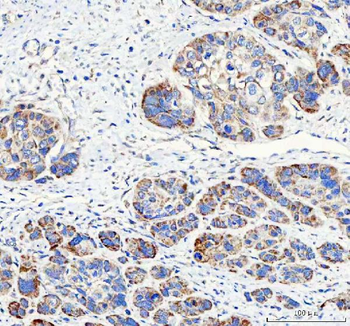

10 μg, 100 μgAnti-PAPSS2 Antibody [orb1743841]

ELISA, FC, IF, IHC, WB

Human, Mouse, Rat

Rabbit

Polyclonal

Unconjugated